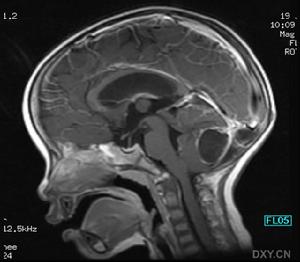

②結核菌素試驗(PPD)陽性同時腦部X-線檢查符合非進行性結核病,痰菌陰性,過去未接受過正規抗結核治療者;

本文2例既往無神經系統疾病史,在用較大劑量異煙肼治療中突然出現抽搐及癲癇樣發作,當即中止用藥,同時給大劑量維生素B6,使症狀較快緩解,表明癲癇發作為異煙肼副反應。異煙肼對中樞神經的毒性反應,是通過拮抗維生素B6而使γ-氨基丁酸(GABA)合成減少所致。GABA是廣泛分布於體內的中樞性抑制性遞質,它的減少造成中樞神經興奮性過度增強,輕則失眠,反射亢進,肌肉抽搐,重則癲癇發作[1]。而癲癇一旦發作,表現為持續狀態,即全身抽搐頻繁,緩解期很短,持續昏迷。